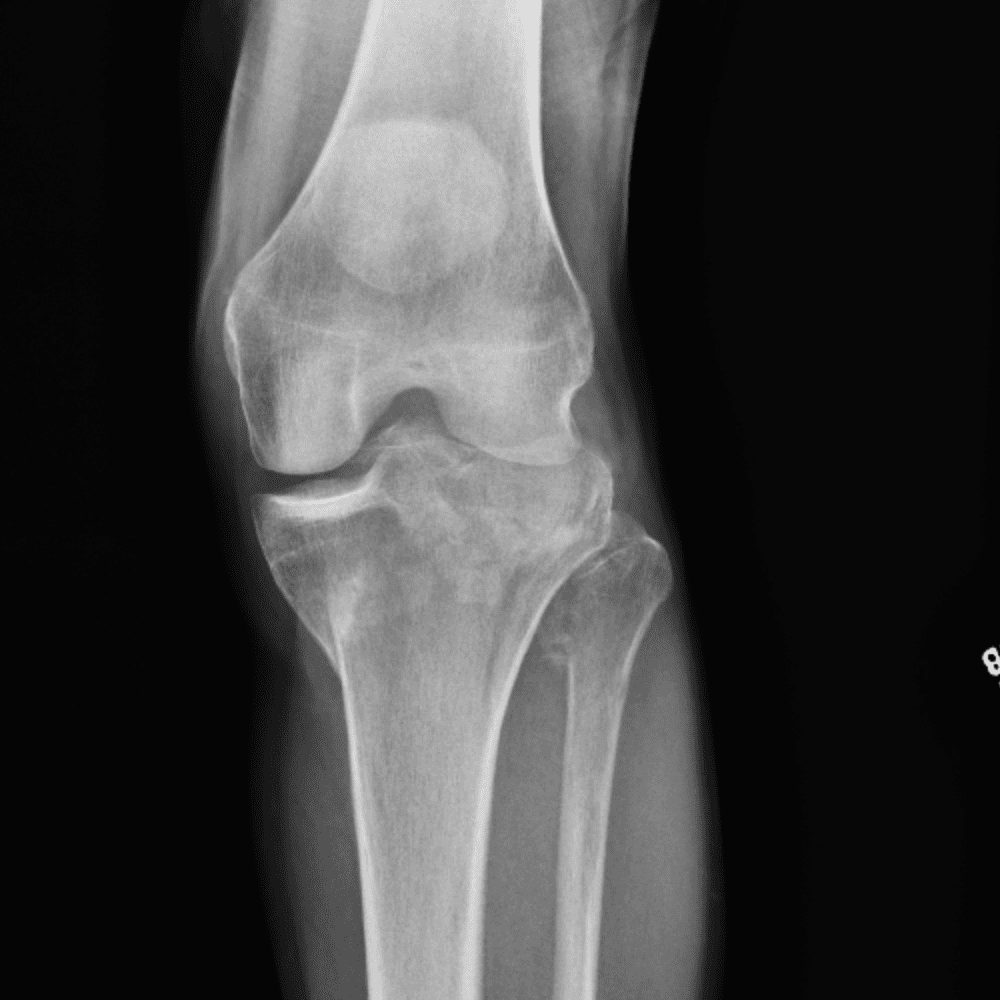

Simula o plantão incluindo casos sutis ou difíceis e alguns normais.